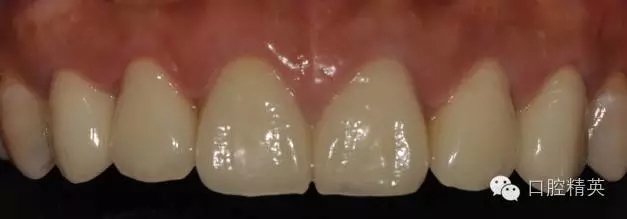

修復(fù)體完成口內(nèi)照片